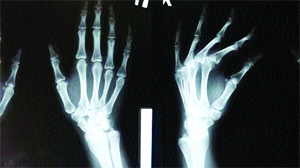

ਬੀਜਿੰਗ : ਚੀਨ ਦੇ ਜ਼ੇਜਿਆਂਗ ਸੂਬੇ ਵਿੱਚ ਮੈਡੀਕਲ ਖੋਜੀਆਂ ਨੇ ਅਜਿਹਾ ਗੂੰਦ ਵਿਕਸਤ ਕੀਤਾ ਹੈ, ਜਿਹੜਾ ਟੁੱਟੀ ਹੱਡੀ ਤਿੰਨ ਮਿੰਟਾਂ ਵਿੱਚ ਜੋੜ ਦਿੰਦਾ ਹੈ। ਇਸ ਦਾ ਨਾਂਅ ‘ਬੋਨ-02’ ਰੱਖਿਆ ਗਿਆ ਹੈ। ਖੋਜੀ ਟੀਮ ਦੇ ਮੁਖੀ ਸਰ ਰਨ ਰਨ ਸ਼ਾਅ ਹਸਪਤਾਲ ਦੇ ਹੱਡੀਆਂ ਦੇ ਸਰਜਨ ਲਿਨ ਜ਼ਿਆਂਗਫੇਂਗ ਨੇ ਦੱਸਿਆ ਕਿ ਡੇਢ ਸੌ ਤੋਂ ਵੱਧ ਮਰੀਜ਼ਾਂ ’ਤੇ ਇਸ ਦਾ ਤਜਰਬਾ ਸਫਲ ਰਿਹਾ ਹੈ। ਇਨ੍ਹਾਂ ਮਰੀਜ਼ਾਂ ਦੇ ਸਟੀਲ ਪਲੇਟਾਂ ਪਾਉਣ ਜਾਂ ਪੇਚ ਕੱਸਣ ਦੀ ਲੋੜ ਨਹੀਂ ਪਈ। ਇਹ ਗੂੰਦ ਬਣਾਉਣ ਦੀ ਪ੍ਰੇਰਨਾ ਸਿੱਪੀਆਂ ਤੋਂ ਮਿਲੀ, ਜਿਹੜੀਆਂ ਤੇਜ਼ ਸਮੁੰਦਰੀ ਲਹਿਰਾਂ ਦੇ ਬਾਵਜੂਦ ਪੁਲਾਂ ਤੇ ਚੱਟਾਨਾਂ ਨਾਲ ਚਿੰਬੜੀਆਂ ਰਹਿੰਦੀਆਂ ਹਨ। ਗੂੰਦ ਨੂੰ ਇੰਜੈਕਸ਼ਨ ਨਾਲ ਹੱਡੀ ’ਤੇ ਪਾਇਆ ਜਾਂਦਾ ਹੈ। ਇਹ ਹੱਡੀ ਦੇ ਠੀਕ ਹੋਣ ਤੋਂ ਬਾਅਦ ਛੇ ਮਹੀਨਿਆਂ ’ਚ ਸਰੀਰ ਵਿੱਚ ਕੁਦਰਤੀ ਤੌਰ ’ਤੇ ਘੁਲ-ਮਿਲ ਜਾਂਦਾ ਹੈ। ਇਸ ਤਰ੍ਹਾਂ ਪਹਿਲੀ ਸਰਜਰੀ ਦੌਰਾਨ ਅੰਦਰ ਪਾਏ ਸਟੀਲ ਦੀ ਛੜ ਆਦਿ ਕੱਢਣ ਲਈ ਦੁਬਾਰਾ ਸਰਜਰੀ ਦੀ ਲੋੜ ਨਹੀਂ ਰਹਿੰਦੀ।